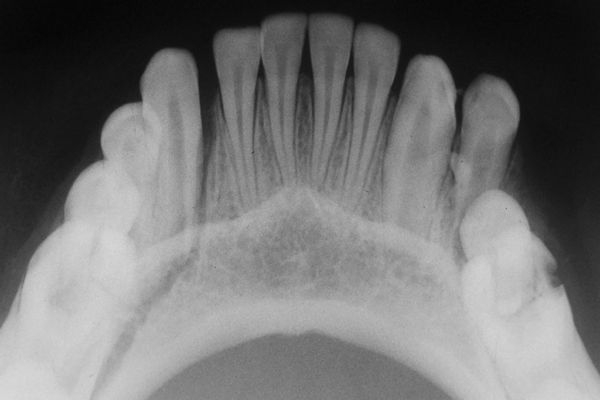

Стоматологические Исследования: Рентген Инвагинации Зубов